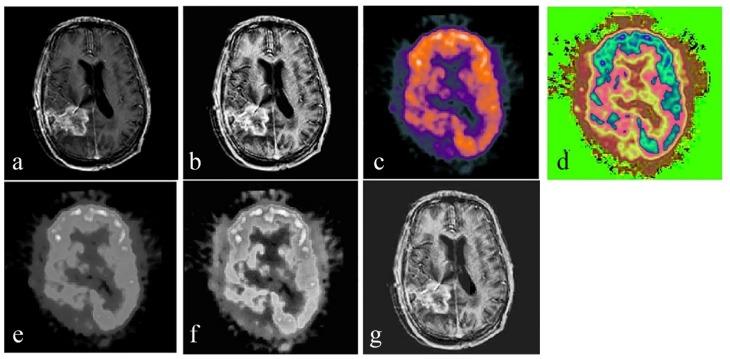

For the fusion of MRI gray scale images and PET color images, we used lesion region extracting based on the digital Curvelet transform (DCT) method. As curvelet transform has a better performance in detecting the edges, regions in each image are perfectly segmented. Curvelet decomposes each image into several low- and high-frequency sub-bands. Then, the entropy of each sub-band is calculated. By comparing the entropies and coefficients of the extracted regions, the best coefficients for the fused image are chosen. The fused image is obtained via inverse Curvelet transform. In order to assess the performance, the proposed method was compared with different fusion algorithms, both visually and statistically.

The analysis of the results showed that our proposed algorithm has high spectral and spatial resolution. According to the results of the quantitative fusion metrics, this method achieves an entropy value of 6.23, an MI of 1.88, and an SSIM of 0.6779. Comparison of these experiments with experiments of four other common fusion algorithms showed that our method is effective.

对于MRI灰度图像与PET彩色图像的融合,我们采用基于数字曲波变换(DCT)方法的病变区域提取。由于曲波变换在检测边缘方面具有更好的性能,每个图像中的区域都能被完美分割。曲波将每个图像分解为几个低频和高频子带。然后,计算每个子带的熵。通过比较提取区域的熵和系数,选择融合图像的最佳系数。通过逆曲波变换获得融合图像。为了评估性能,将所提出的方法与不同的融合算法在视觉和统计方面进行比较。

结果分析表明,我们提出的算法具有高光谱和空间分辨率。根据定量融合指标的结果,该方法的熵值为6.23,互信息(MI)为1.88,结构相似性指数测量值(SSIM)为0.6779。将这些实验与其他四种常见融合算法的实验进行比较表明,我们的方法是有效的。